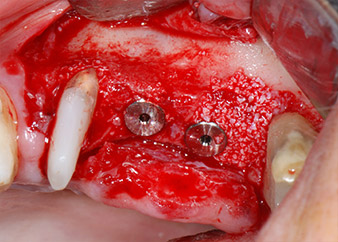

A continuación, los implantes (Restore, Keystone Dental, 3,75 mm de diámetro, 8,0 mm de longitud) se colocaron con el motor de implantes (figuras 11 y 12).

listos para los tornillos de cubierta

Fig. 12: Los dos implantes están colocados y listos para los tornillos de cubierta.